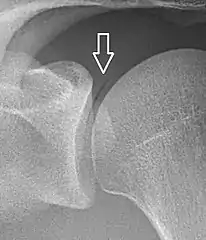

Pneumarthrosis is a common normal finding in shoulders[7] as well as in sternoclavicular joints.[9] It is believed to be a cause of the sounds of joint cracking.[8] It is also a common normal post-operative finding at least after spinal surgery.[10] Pneumarthrosis is extremely rare in conjunction with fluid or pus in a joint, and its presence can therefore practically exclude infection.[8]

A vacuum sign, or vacuum phenomenon, is a normal finding on shoulder X-rays.